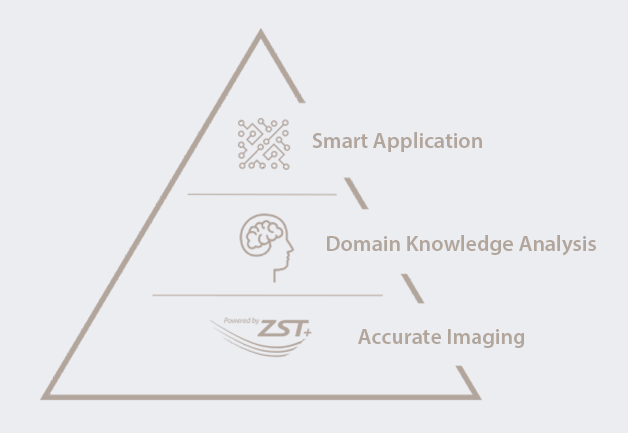

Met de ontwikkeling van de samenleving en de toenemende bezorgdheid over de gezondheidsproblemen van vrouwen, zijn steeds meer vrouwen zich bewust van het belang van regelmatige gynaecologie-onderzoeken met behulp van echografie. De groeiende vraag naar echografisch onderzoek heeft ongetwijfeld geleid tot een nieuwe uitdaging voor echografisten, om nog maar te zwijgen van het feit dat de vraag steeds meer gesegmenteerd is. Om het proces te vereenvoudigen en meer vrouwen te voorzien van hoogwaardige diagnostische echografiediensten, zet Mindray zich in voor innovatie en biedt een volledig pakket slimme oplossingen voor de gezondheidszorg voor vrouwen en kinderen, mogelijk gemaakt door zone intelligence?. Wij hopen de echografisten een 'magisch wapen' in handen te geven waarmee ze meerdere onderzoeksscenario's aankunnen, van pre-zwangerschap en zwangerschap, tot postpartumherstel en pasgeborenen, waardoor hun gezondheid verder wordt beschermd.

Op basis van diepgaande klinische gegevensanalyse en front- en back-end beeldoptimalisatie hebben we een volledig pakket slimme oplossingen voor de gezondheidszorg voor vrouwen en kinderen ontwikkeld om het proces te stroomlijnen en de nauwkeurigheid van ultrasone scans te verbeteren, voor een effici?ntere diagnose. Tegelijkertijd, met het klinische scenario als leidraad, ontwerpen we het product vanuit het oogpunt van de arts om te voldoen aan de ├®├®n-klik-omschakeling en ├®├®n-klik-beeldvorming voor het scannen van meerdere sc├©nes, waardoor het gemakkelijker te bedienen is. Samen met echografie-experts zetten wij ons in om briljante oplossingen te bieden aan zorgverleners, zodat steeds meer vrouwen en kinderen wereldwijd toegang krijgen tot hoogwaardige echografiezorg.